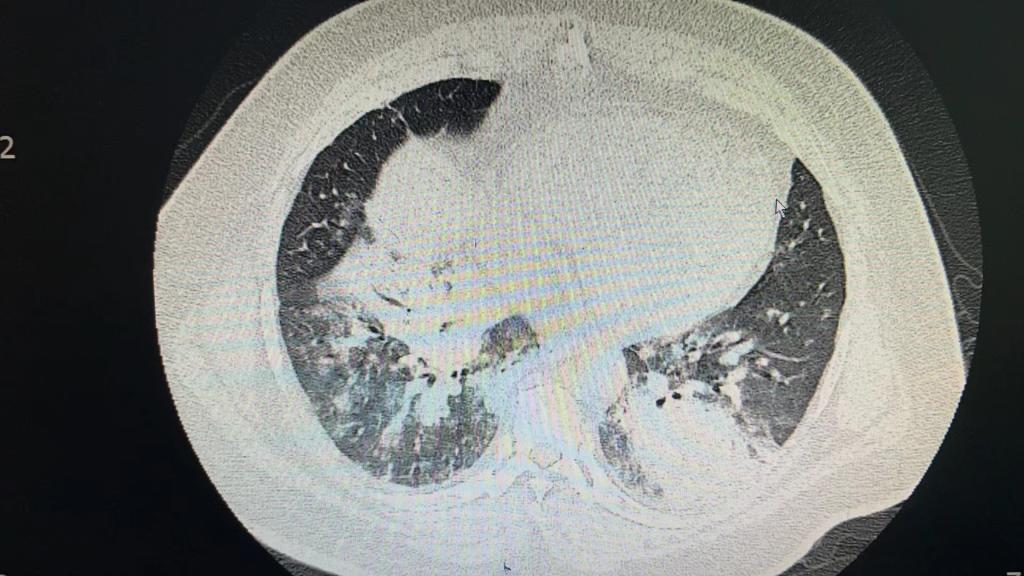

患者以“发热6天伴呼吸衰竭”从外院转入我院EICU,CT呈“白肺”样改变,入院后气管插管呼吸机辅助通气,氧浓度100%,血氧饱和度不到80%,氧合指数只有50,生命岌岌可危。千钧一发之际,ECMO团队迅速全面的病情评估后,紧急启用ECMO支持治疗。

图1 图2腺病毒感染的白肺